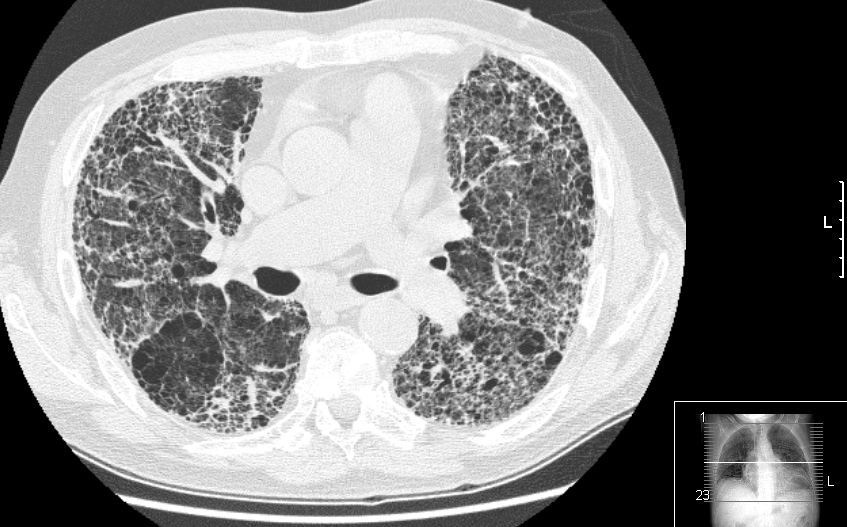

Eficacia de los antibióticos preventivos en la fibrosis pulmonar idiopática

14 diciembre 2020

En pacientes con formas moderadas a graves de la enfermedad, el tratamiento con cotrimoxazol oral no redujo un resultado combinado de mortalidad, trasplante u hospitalización no selectiva en comparación con placebo. JAMA, 8 de diciembre de 2020.